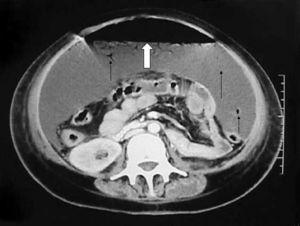

Exponemos el caso de una mujer de 38 años que sufre accidente de tráfico e ingresa en nuestro Centro en situación de shock hipovolémico con fracturas costales múltiples, neumotórax y contusión pulmonar bilateral. Entre las pruebas complementarias realizadas a su ingreso destacan una ecografía y una tomografía axial computarizada (TAC) de abdomen normales. Durante su estancia en el Servicio de Medicina Intensiva se repite dos veces la ecografía abdominal, que muestra una pequeña cantidad de líquido perihepático y entre asas y una colección líquida con ecos en su interior en región prehepática muy superficial en relación con hematoma de pared. A los 19 días, por intolerancia a la alimentación enteral y desarrollo de distensión abdominal se realiza otra TAC (fig. 1) que muestra una gran cantidad de líquido ascítico con gas en su interior en forma de burbujas (flechas negras) y un gran nivel hidroaéreo (flecha blanca). Se interviene a la paciente de urgencia, encontrando un gran neumoperitoneo y aproximadamente 2 litros de líquido intestinal secundario a un desgarro del meso del íleon terminal con necrosis completa y perforación de unos 30 cm.

Figura 1. Nivel hidroaéreo abdominal.